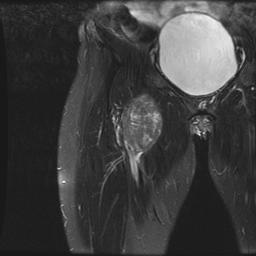

Leimyosarcoma Femoral Vein MRI Coronal T2Leimyosarcoma Femoral Vein MRI Axial T2